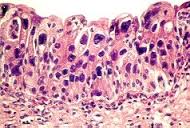

La mucosa del tracto urinario está compuesta por un epitelio estratificado con un promedio de 7-8 capas de células especializadas conectadas a una membrana basal. El grosor de la mucosa vesical varía dependiendo del estado de la misma. Cuando está distendida, solo hay escasas capas de células uroteliales, cuando está desocupada presenta un epitelio grueso estratificado. Las células de las capas profundas son pequeñas con un único núcleo. Las células superficiales son más grandes y con frecuencia multinucleadas con 2 a 55 núcleos. Cada célula superficial cubre dos o más células basales. Por esta razón son llamadas células sombrilla. El urotelio de la vejiga normal puede mostrar múltiples invaginaciones epiteliales llamadas nidos de von Brunn. Estos pueden estar recubiertos de células columnares secretoras de moco en vez de urotelio. Cuando se encuentran distendidos con moco la apariencia histológica se denomina cistitis cística o cistitis glandular.